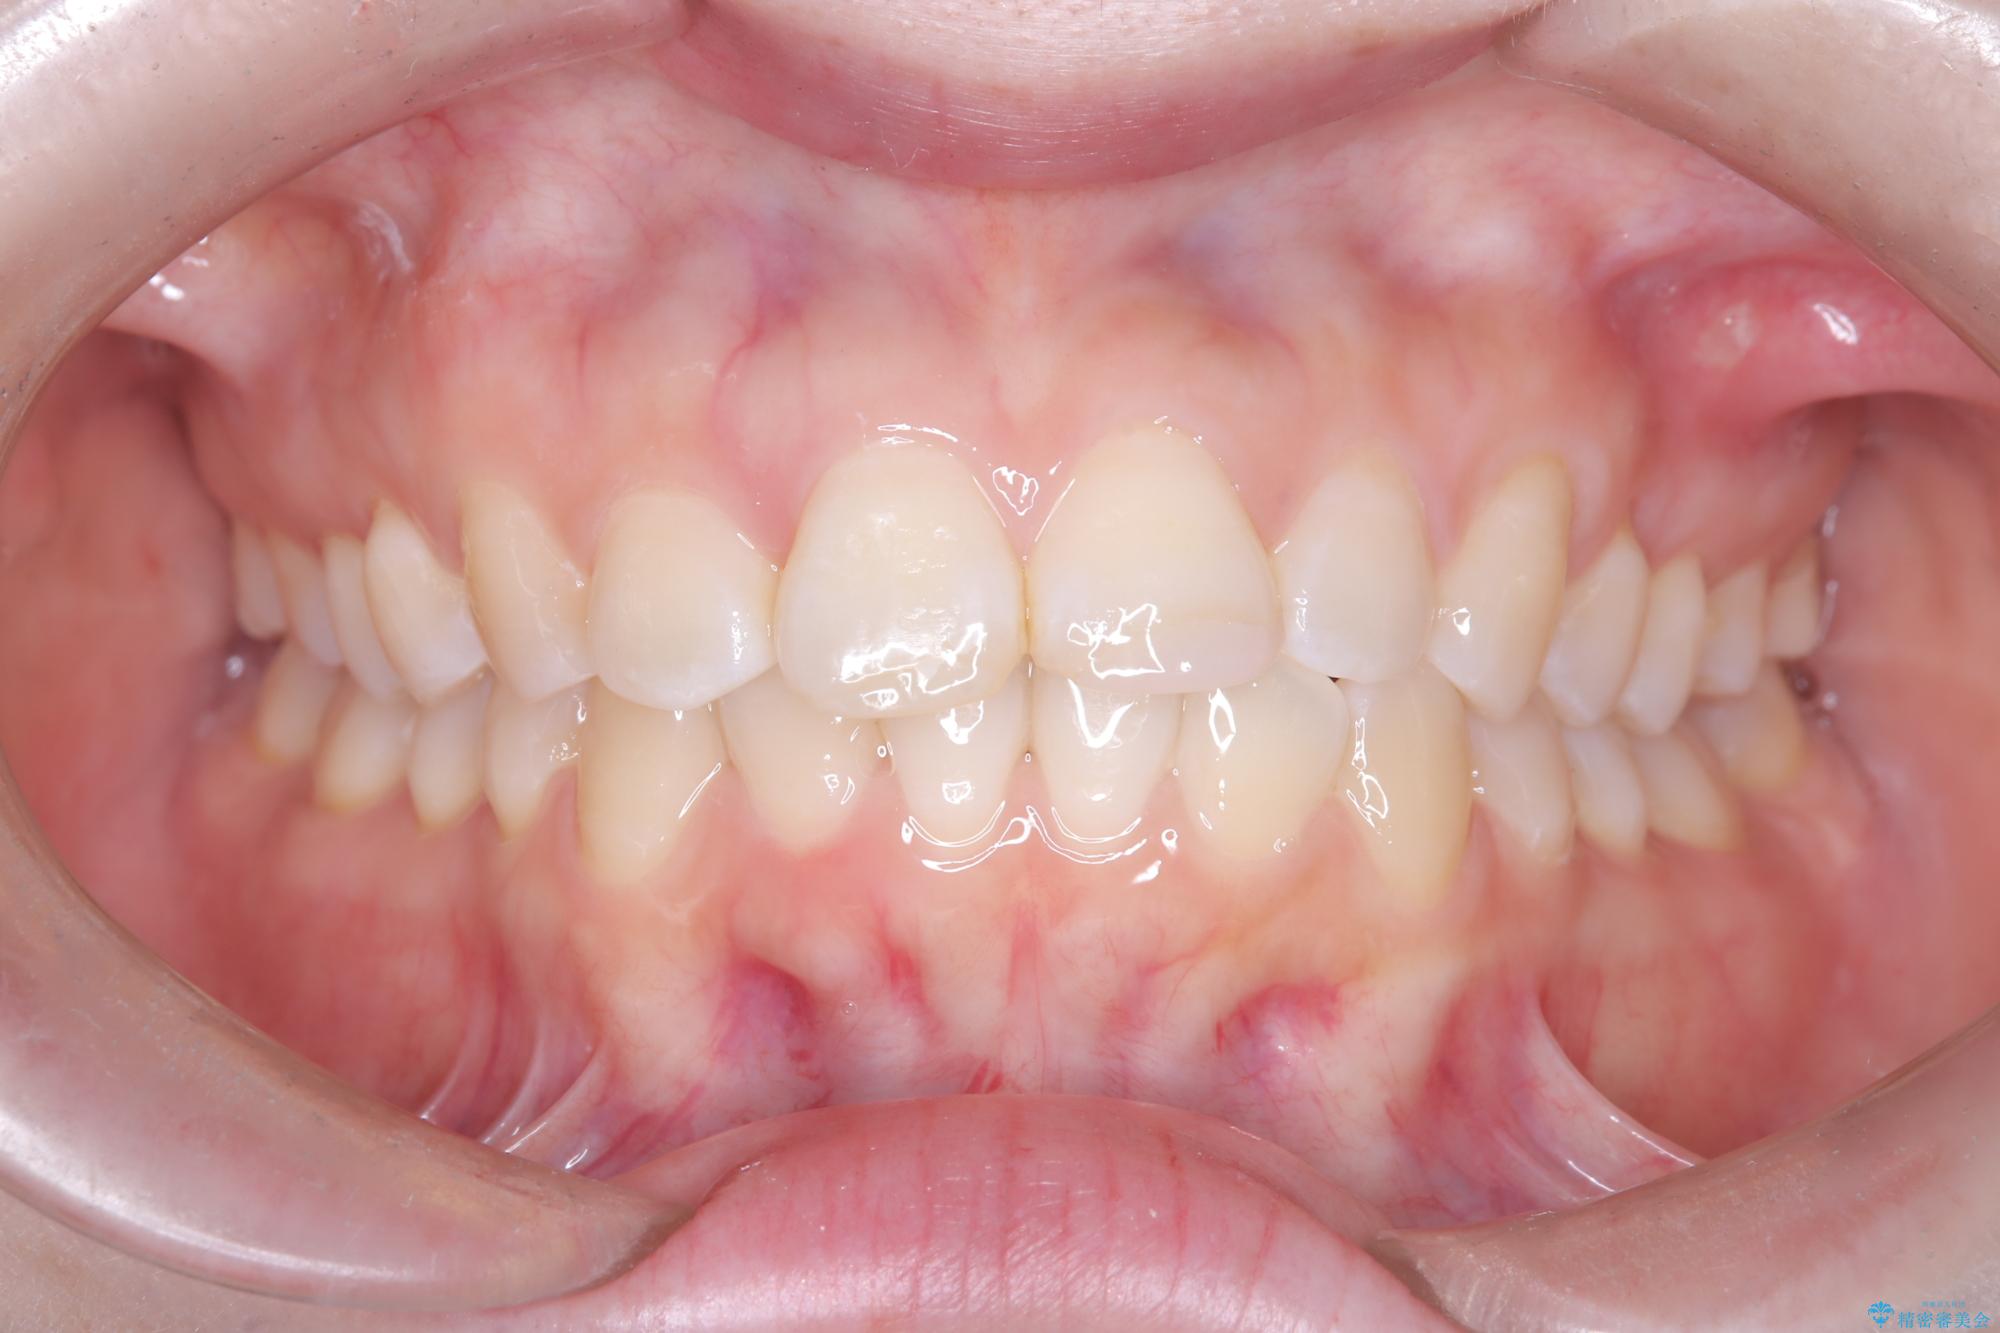

- 前歯のデコボコ(叢生)を気にされてご来院されました。精密な検査の結果、歯が並ぶスペースが不足していることが判明。患者様のご希望から、透明で目立ちにくいインビザライン(マウスピース矯正)による治療計画を立案しました。抜歯を避け、奥歯全体を奥へ動かす遠心移動という方法でスペースを確保し、前歯の叢生を解消することを目指します。

今回の矯正治療では、透明なマウスピース型の装置インビザラインを使用しました。この装置は取り外し可能で、日常生活で目立ちません。治療は、緻密に計算された計画に基づき、段階的に作製されたマウスピースを交換していくことで、奥歯から順に全体を後方へ移動させる遠心移動を実施。これにより、前歯を並べるための十分なスペースが確保され、デコボコが解消されました。抜歯することなく、機能的にも審美的にも整った美しい歯並びを獲得していただけました。